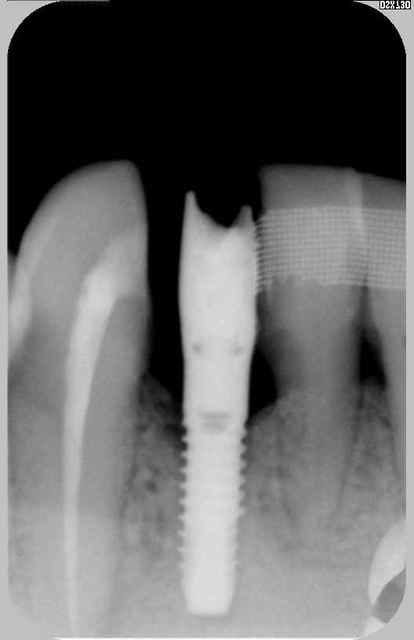

en ragardant le sujet vis cassée je vous donne des nouvelles de l'implant col cassé deux ans après et du petit bricolage généré dessus.

nous avons réalisé une armature sur la barre avec un petit fraisage et scellé le tout.

comme j'ai la chance que les patients fassent le suivi

rvg en 2011

pseudo réossification autour de mon bricolage si on fait attention faut dire que c'est un beau cône morse (!)

Euh je ne veux pas être négatif mais je dirai plutôt une cratérisation établie; ton os arrivait à la spire distal n°10 (à l'origine) maintenant il est bien en dessous :-(

Désolé mais effectivement c'est une très belle gestion de complication, je te félicite pour celà même si je ne partage pas ton optimisme "osseux".

pourquoi penses tu que je parle de "pseudo" réossification et de cone morse : aucune étanchéité autour du bricolage qui présente encore moins d'étanchéité qu'un connectique à plat

les contraintes que montraient Haig sont bien toujours présentes même si soulagées par le fait que l'on ait "acastillé" l'autre coté .

il s'agit d'un sauvetage la corticale en linguale est toujours présente mais poche en vestibulaire car l'axe de cet implant n'est pas non plus idéal en vestibulo lingual comme mésio distal ya pas de raison:-))